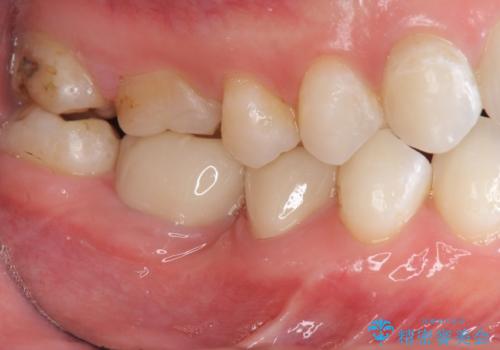

銀歯を白くしたい セラミック治療

色調の自然さや、噛み合わせが改善され、満足いただくことができました。

- 26.4万円(ジルコニアクラウン×2・仮歯×2)費用は治療当時の料金となります